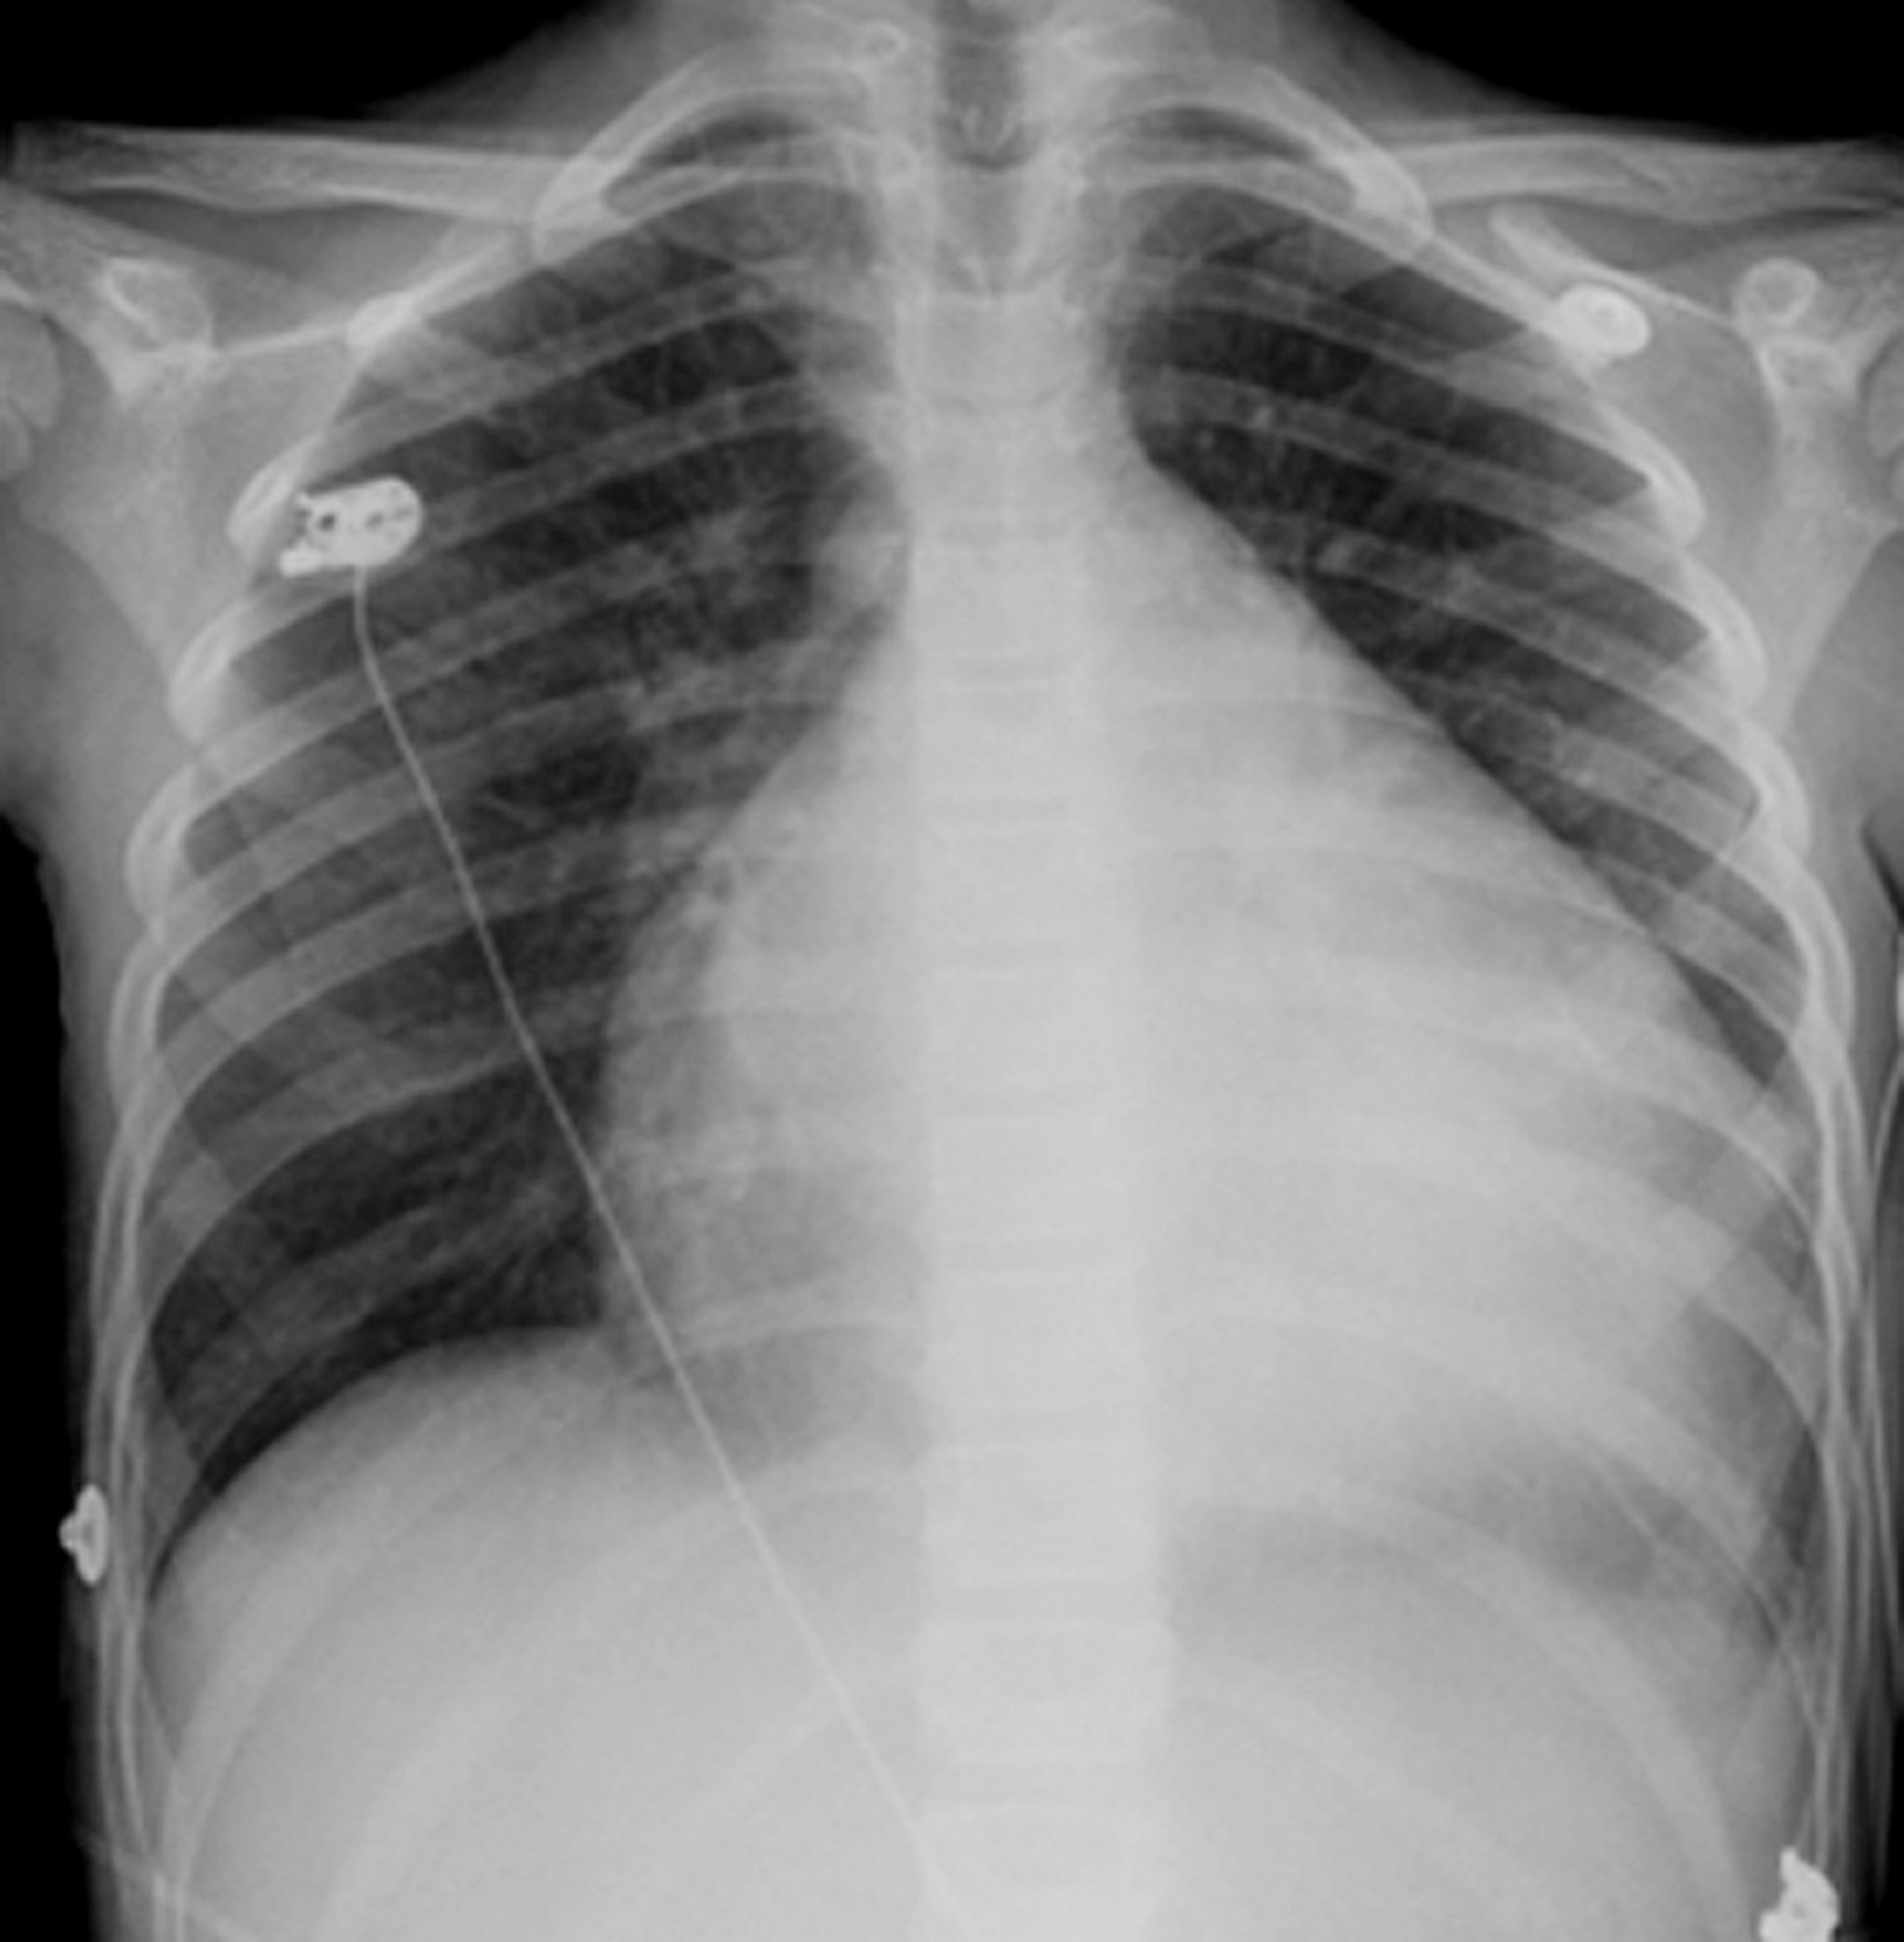

Pembesaran Jantung

Jantung adalah struktur berbentuk bulat dan berwarna putih di tengah dada. Biasanya jantung memakan ruang kurang dari setengah dada, namun, pada orang ini yang mengalami pembesaran jantung (kardiomiopati), jantung hampir memenuhi 3/4 dimensi dada.